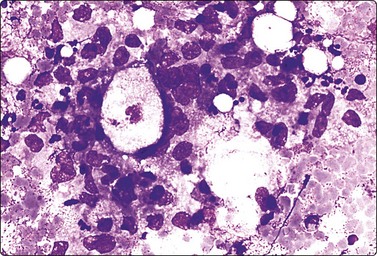

image image

Fig. 7.1 Radiation-induced atypia

(A) The epithelial cells in this irregular cluster show considerable nuclear enlargement, pleomorphism and hyperchromasia, but also some degenerative changes such as loss of nuclear structure (MGG, HP); (B) Corresponding tissue section (H&E, IP).